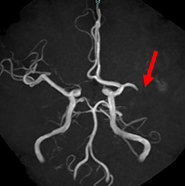

脳動脈瘤

【脳動脈瘤】

コイル塞栓術後

【コイル塞栓術後】